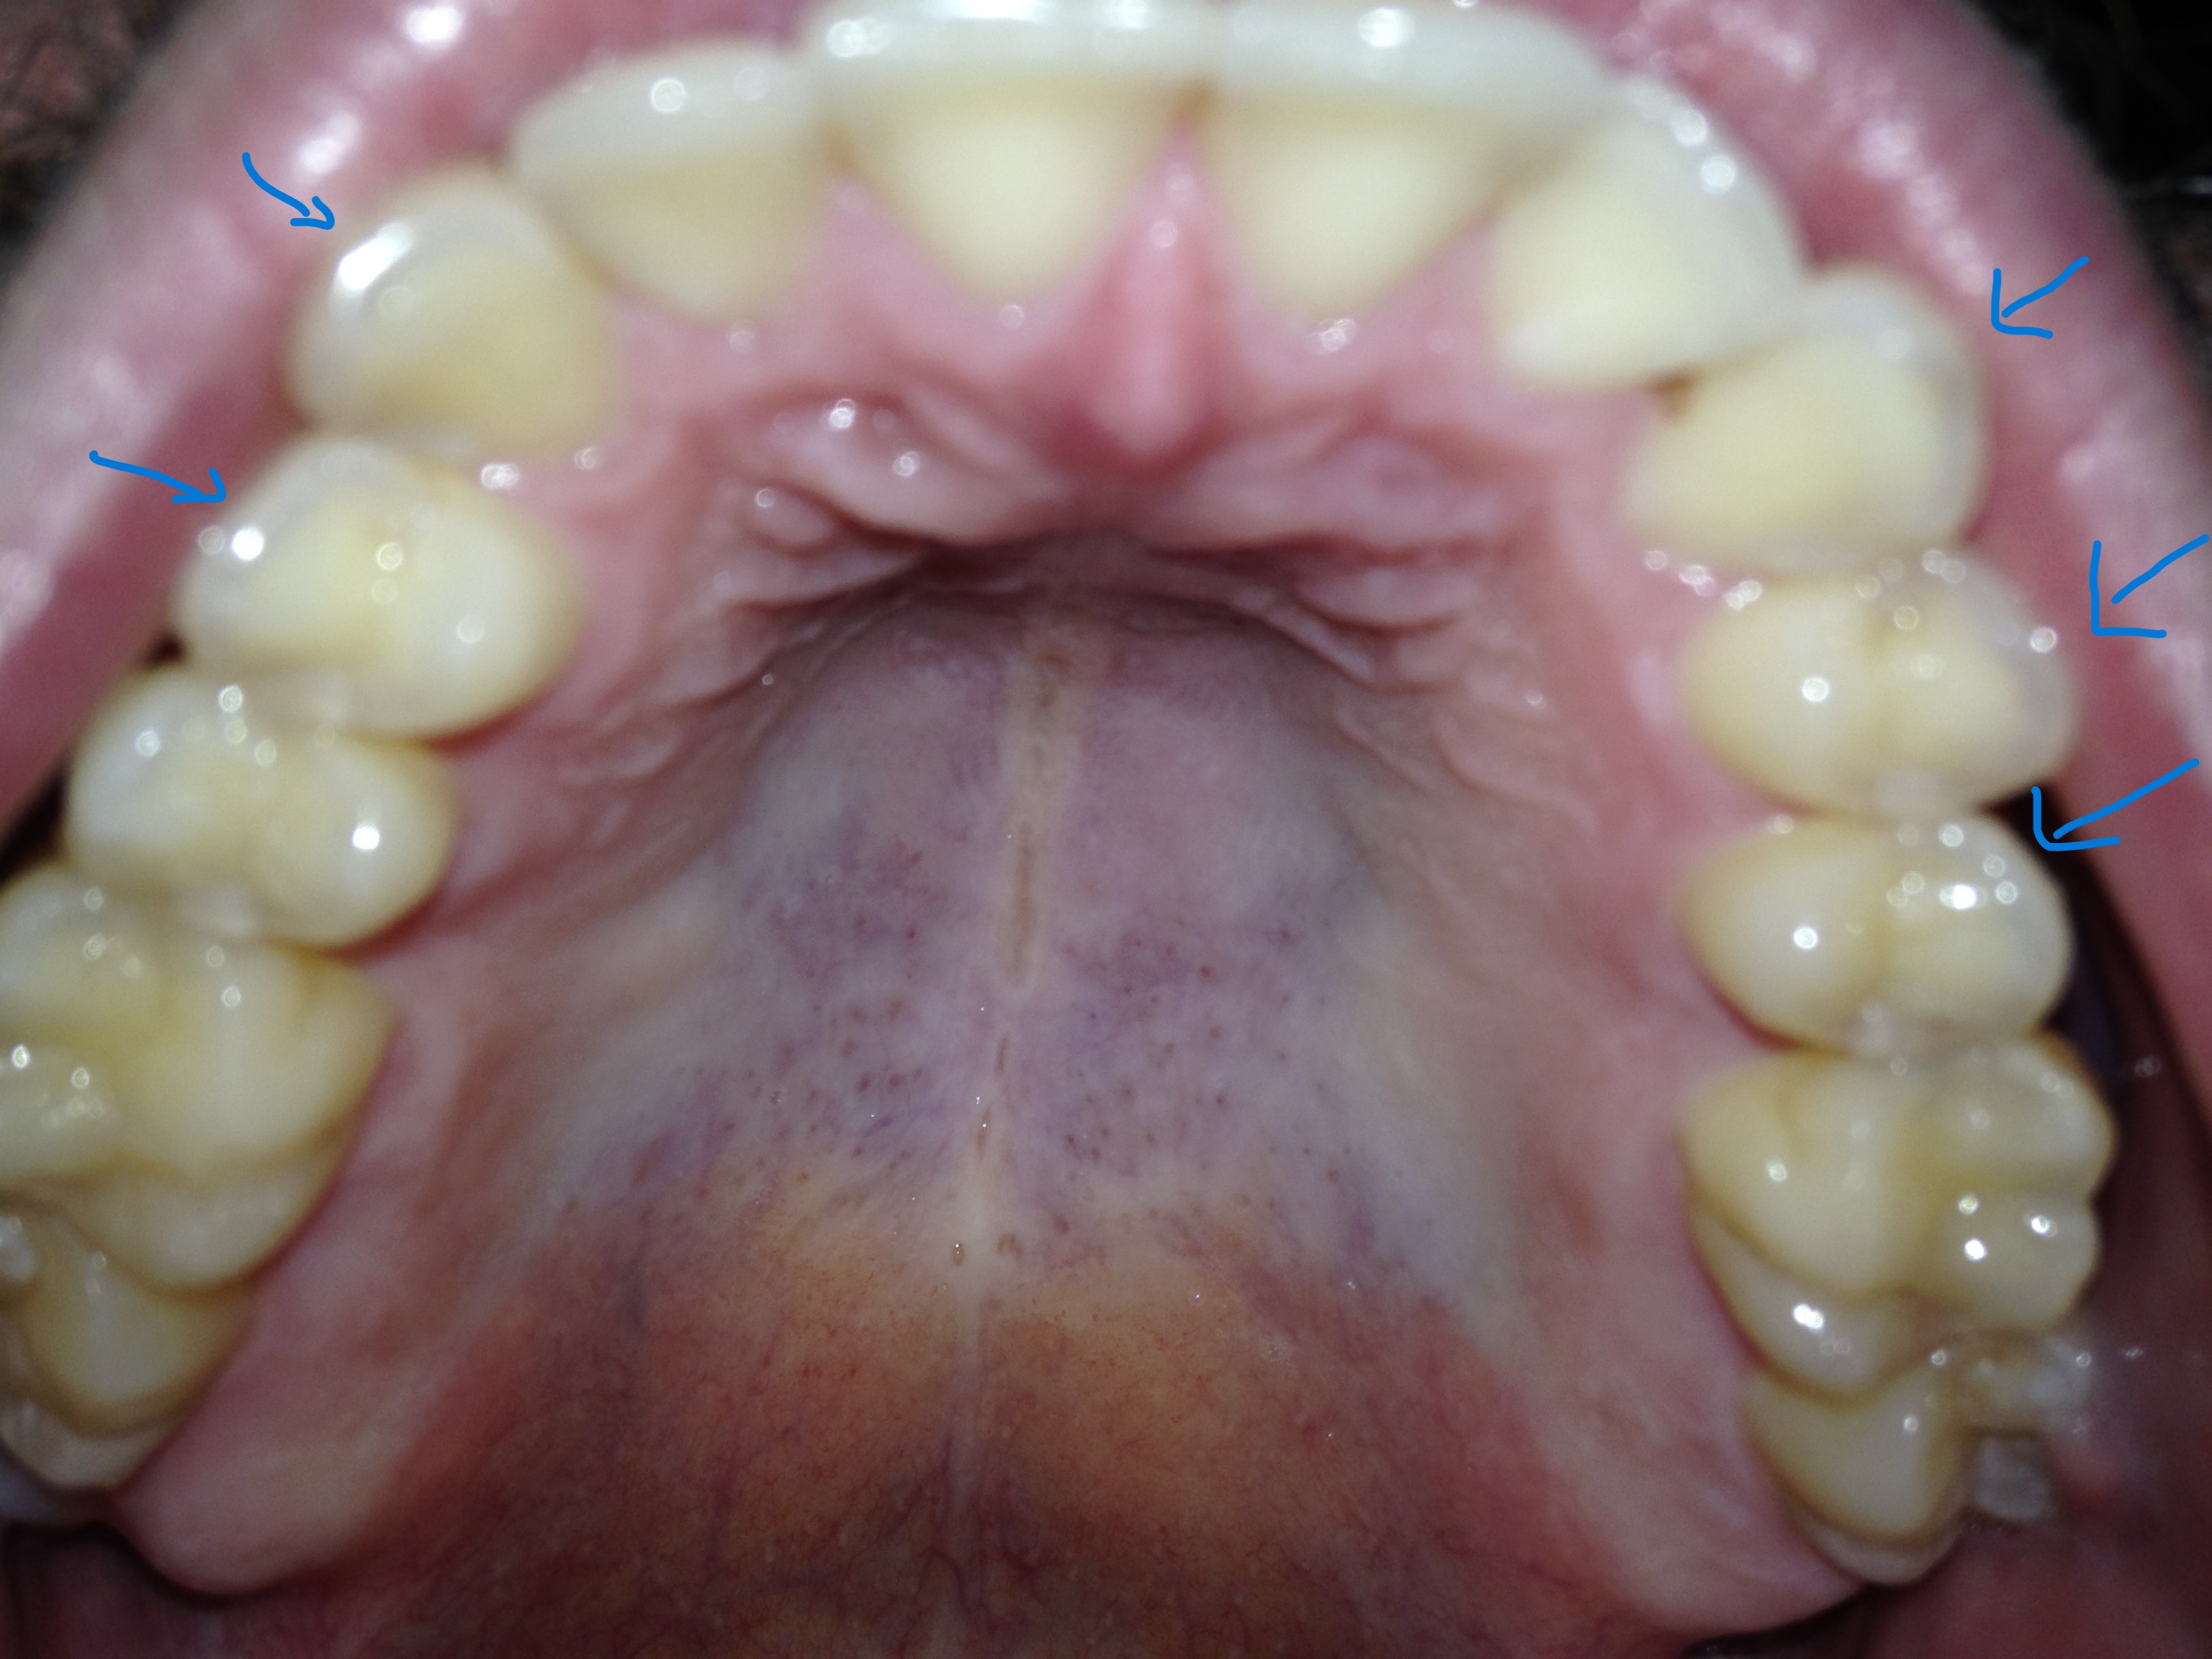

Ik zie dat de randen van mijn tanden en kiezen best doorzichtig zijn en las dat dit tanderosie kan zijn, daarnaast zie ik de dentine. Ik nuttig geen suikers of zuren dus ik begrijp niet waarom ik dit zou hebben. Daarnaast heeft de tandarts er nooit wat over gezegd. De eerste foto is van vandaag, de andere van 2015 (foto's van de boventanden). Als ik deze twee foto's vergelijk zie ik dat er geen verschil is en dat bij beide foto's evenveel doorzichtigheid en dentine te zien is.

De tweede foto is inderdaad niet heel scherp, maar als je goed kijkt zie je dezelfde doorzichtigheid (heb een foto met pijltjes toegevoegd). Ik eet best gezond en mondhygiëne is ook best goed, ik vermijd suikers en drink voornamelijk water. Geen idee wat de PH is helaas, vind het ook apart dat mijn tandarts er nooit wat over heeft gezegd.